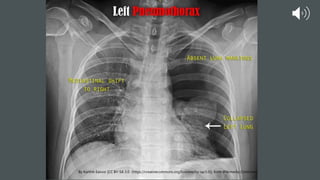

Yellow arrow points to thin white line

(visceral pleural), beyond which, there

are no vascular markings. This line is

the best sign for a pneumothorax.

Red arrow points to the intrapleural

space (typically not visible), filled with

air (black) and no vascular markings

Yellow arrow pointsto thin white line (visceral pleural), beyond which, there are no vascular markings. This line is the best sign for a pneumothorax. Red arrow points to the intrapleural space (typically not visible), filled with air (black) and no vascular markings